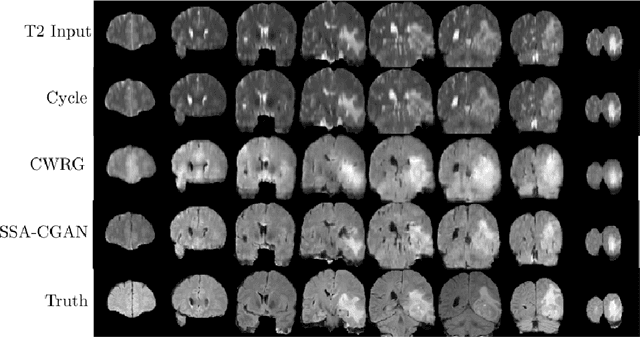

Abstract:Magnetic Resonance Imaging (MRI) of the brain can come in the form of different modalities such as T1-weighted and Fluid Attenuated Inversion Recovery (FLAIR) which has been used to investigate a wide range of neurological disorders. Current state-of-the-art models for brain tissue segmentation and disease classification require multiple modalities for training and inference. However, the acquisition of all of these modalities are expensive, time-consuming, inconvenient and the required modalities are often not available. As a result, these datasets contain large amounts of \emph{unpaired} data, where examples in the dataset do not contain all modalities. On the other hand, there is smaller fraction of examples that contain all modalities (\emph{paired} data) and furthermore each modality is high dimensional when compared to number of datapoints. In this work, we develop a method to address these issues with semi-supervised learning in translating between two neuroimaging modalities. Our proposed model, Semi-Supervised Adversarial CycleGAN (SSA-CGAN), uses an adversarial loss to learn from \emph{unpaired} data points, cycle loss to enforce consistent reconstructions of the mappings and another adversarial loss to take advantage of \emph{paired} data points. Our experiments demonstrate that our proposed framework produces an improvement in reconstruction error and reduced variance for the pairwise translation of multiple modalities and is more robust to thermal noise when compared to existing methods.